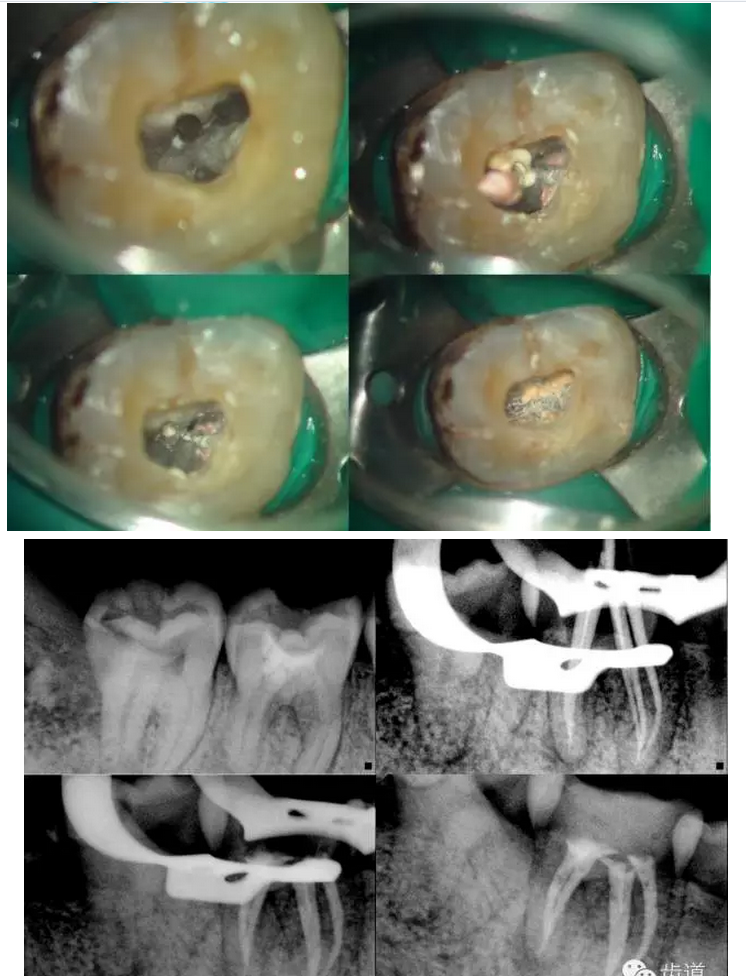

鄭玉琪:尋找迷失的根管第二季——容易遺漏的根管

上頜第一磨牙:多為3-4個(gè)根管,MB2發(fā)生率約為60%;

下頜第一磨牙:為3-4個(gè)根管,遠(yuǎn)中雙根管的發(fā)生率為51.4% 左右,側(cè)支根管發(fā)生率為30%左右;